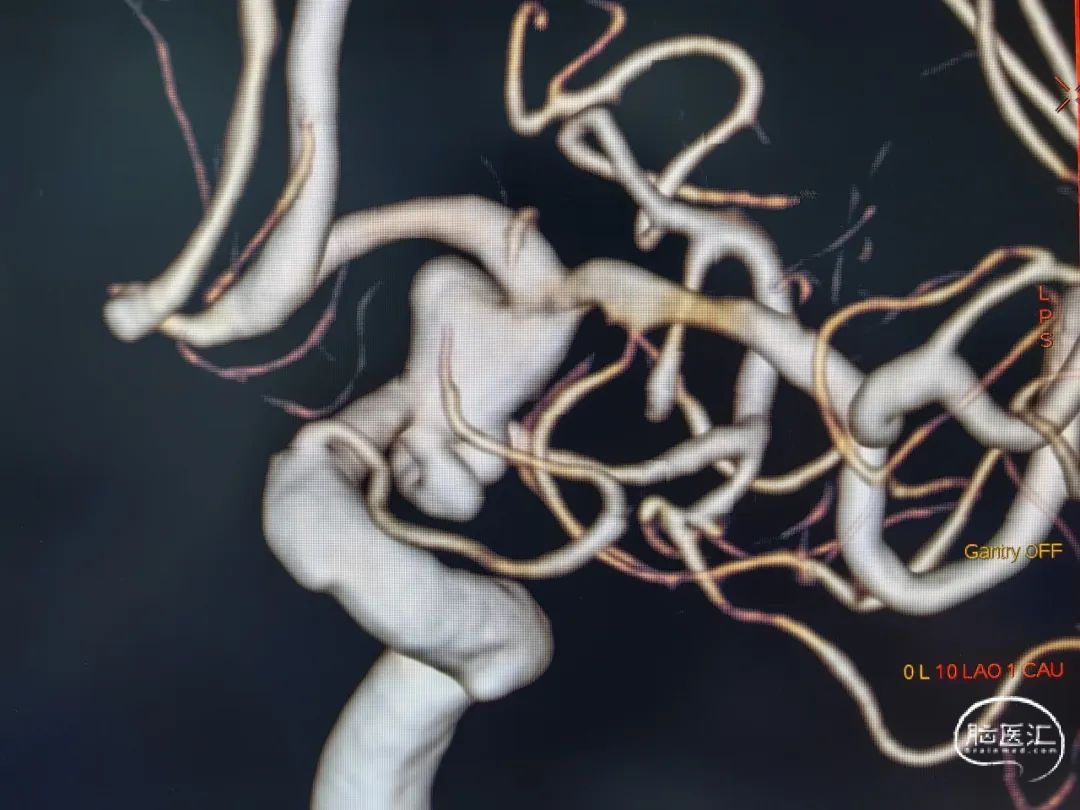

急诊DSA:

左颈内动脉后交通段多发动脉瘤

蛛网膜下腔出血(Hunt-Hess:2级)

交通段颈内动脉膨大,形态不规则且多发动脉瘤,故选择密网支架辅助弹簧圈栓塞。

弹簧圈栓塞破裂动脉瘤,PED重建病变部位的交通段颈内动脉。